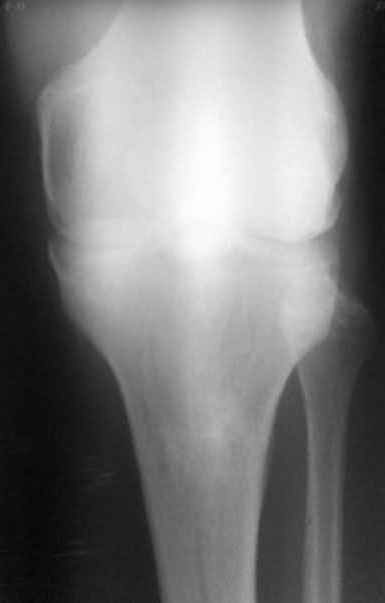

пациент наконец то объявился вновь и мы смогли выполнить новые снимки как лежа так и в нагрузке

если у вас остались силы, давайте обсудим